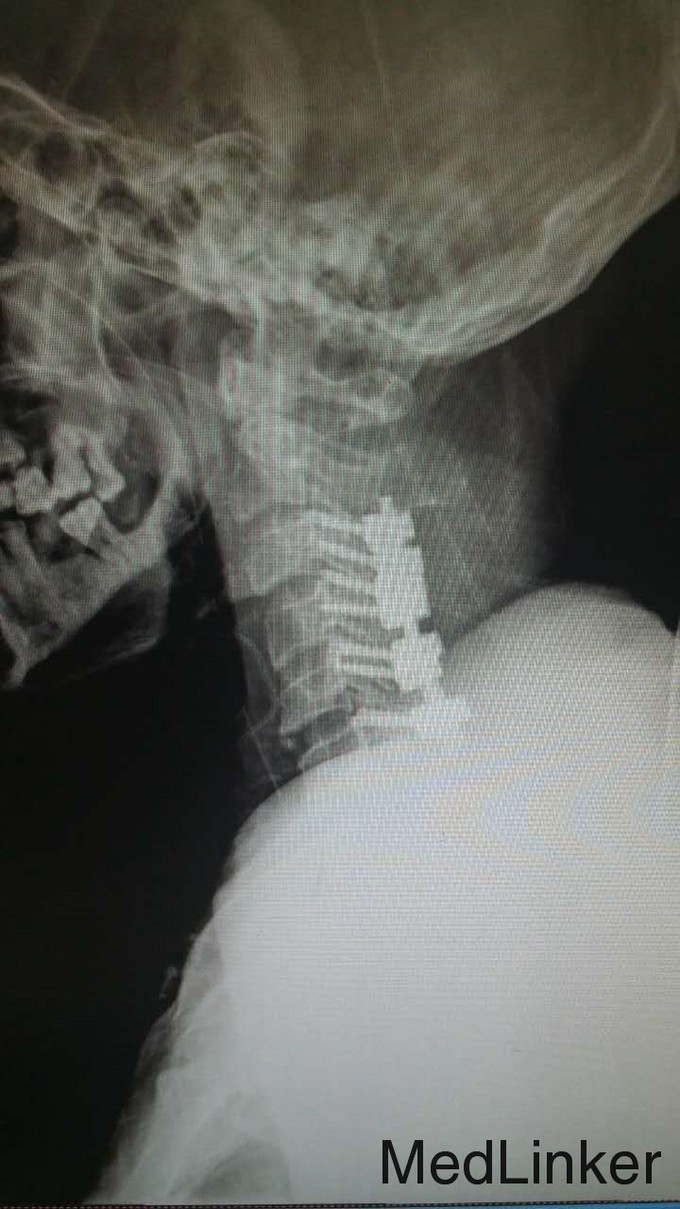

主诉:头颈部重物咂伤5小时伴四肢瘫 病史:入院5小时前,头颈部被门板砸伤,伤后全身疼痛,伴四肢瘫。

查体:T4平面以下痛觉消失,四肢肌力0级。双侧病理征阳性。 辅检:全身CT示:C4左侧椎扳、侧块、C5-6左侧横突多发骨折,C5椎体压缩骨折,C4椎体滑脱,颅内未见明显血肿,胸腹盆末见明显外伤行病变。头颅MRI示:C3-6水平颈髓出血伴水肿。

诊断:1.C3-6水平颈髓损伤出血伴水肿,2.C4左侧椎扳、侧块、C5-6左侧横突多发骨折,3.C5椎体压缩骨折,4.C4椎体滑脱(Ⅰ度) 治疗:伤后5天,予行C3-6椎板切除、椎管减压,侧块固定融合术

随访:现术后10天,患者右上肢肌力4级,右下肢肌力1-2级,左上肢肌力1级,左下肢肌力0级。 讨论:患者颈椎脊髓损伤,脊髓出血伴水肿,局部压力高,行减压后缓解局部压力,有助于脊髓功能恢复。